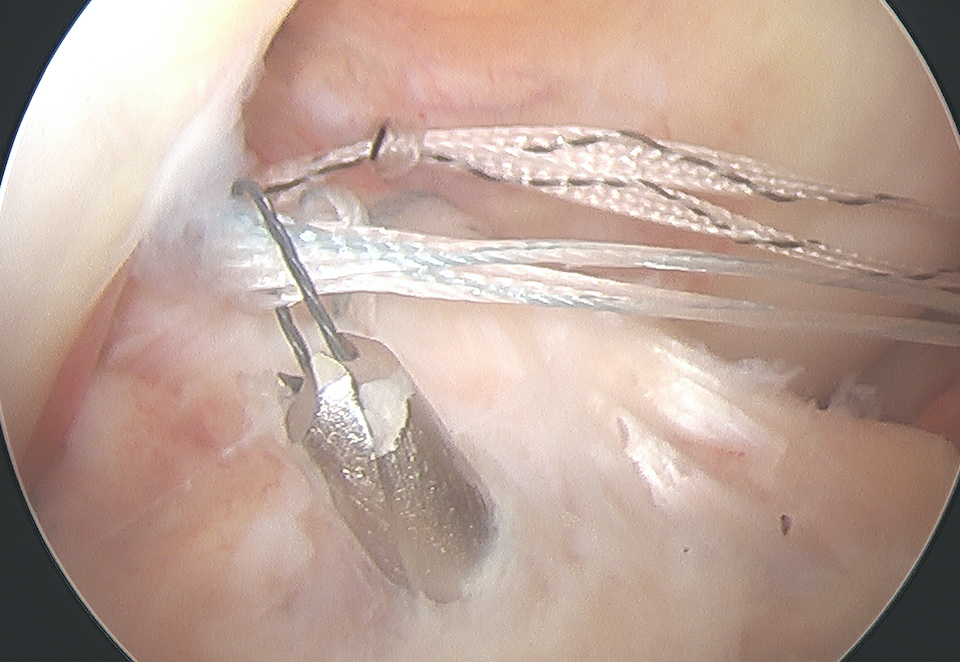

Arthroscopic suture fixation

Fragment flipped and insertion debrided Avulsion fragment reduction Passage of two loop sutures with scorpion

ACL tibial jib with beath pin Beath pin cannulated, loop wire passed Retrieval of sutures

Technique

Clean haematoma, ensure can reduce fragment with probe

- can consider temporary fixation with K wire

- arthroscopic suture passer (i.e. arthrex knee scorpion)

- pass sutures x 2 through ACL above bony fragment

- cannulas can be useful for suture management

Reduce fragment and hold with ACL tibial guide

- medial tibial incision, pass beath pins x 2 (preferable cannulated)

- 1 cm between tunnels

- beath pins exit through bony fragment

- retrieve sutures

- reduced fragment, knee in full extension

- tie over bony bridge or over cortical button

Technical note

1. Passing sutures anterior to the bony fragment rather than through may help anatomical reduction

2. Companies make cannulated beath pins, allowing suture loops to be passed up the pins